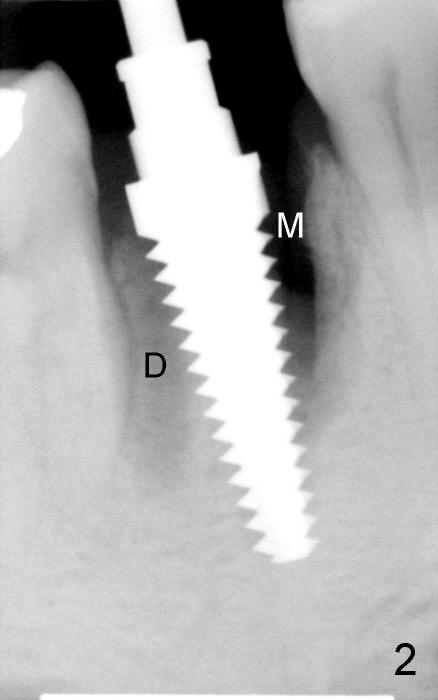

Three weeks postop, the gingiva is healthy around the implant (Fig.5 I). There is no symptom or sign of the infection (>, as compared to Fig.1). The abutment has accomplished its transient function (A, the perio dressing having dislodged) and is subsequently removed (Fig.6, to reduce micromovement of the implant and cheek and tongue bite). The 7 mm implant (I) does not look too big in its new home (alveolus). Four months postop, the mesial socket appears to have normal bony trabecular patterns (Fig.7, as compared to Fig.3).

The next time the patient returns is 8.5 months postop (Fig.8,9). When an immediate provisional is not provided, the patient tends not to return early. In fact, retention of an immediate provisional and confidence in it by the patient promotes early finish of treatment (permanent crown).